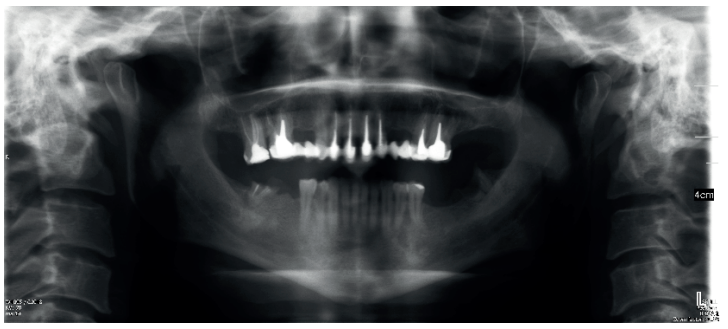

El paciente aporta como estudio radiológico una ortopantomografía (OPG), (Figura 1). Se realizaron radiografías periapicales (Figuras 2 y 3), así como exploración clínica incluyendo la valoración periodontal de los dientes afectados, sin observar profundidades de sondaje aumentadas que pudieran indicar la existencia de lesiones endoperiodontales.

Para el correcto diagnóstico de lesiones radiolúcidas a nivel periapical es importante disponer de imágenes radiológicas que muestren con precisión la situación y tamaño de dichas lesiones. En nuestro caso el paciente aportaba una ortopantomografía. Este tipo de radiografía no es adecuada para el diagnóstico en endodoncia. La radiografía periapical aporta mejor definición, especialmente a nivel anterior, ya que presenta una menor distorsión. Actualmente el CBCT es la prueba radiológica más fiable, ya que proporciona imágenes en las tres dimensiones del espacio, lo que permite diagnósticos más precisos1,2 .